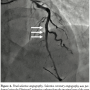

The patient was admitted and coronary angiography was performed on the following day after hydration with 0.9% saline at 1 ml/kg/hour. Subtotal occlusion of the intermediate left anterior descending artery (LAD) was observed (Figure 1). In total, 25 ml contrast medium was used. The blood test did not show further deterioration of the renal function.